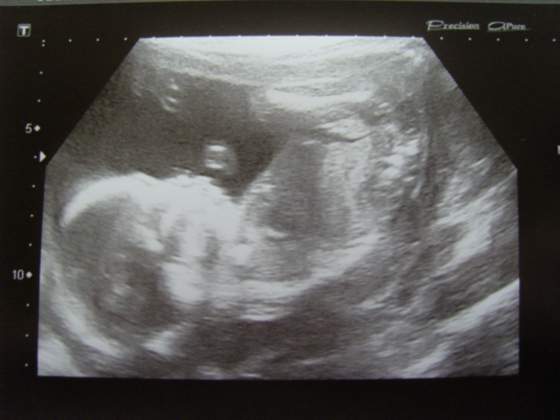

Ja miałam wczoraj wizytę, nie wiem jaka płeć. Lepiej sie nie nastaiwać że się dowiesz bo potem możesz być zawiedziona...